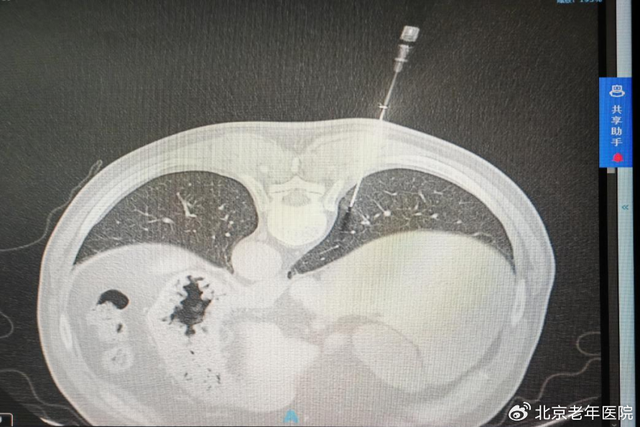

手术过程中,在局部麻醉后,刘前桂主任医师与程刚主任医师、田蓉副主任医师密切协作,先以粗针破皮建立通道,将同轴针精准插入胸膜腔,经CT再次确认进针方向无误后,稳步推进至病灶位置,顺利完成3针穿刺取样。

术前,团队依托CT影像技术,对病灶的大小、位置、深度及与周边肺组织、胸膜腔的关系进行反复精准测量与评估,从穿刺肋间选择、进针角度调整到路径规划,每一个环节都经过严谨论证。